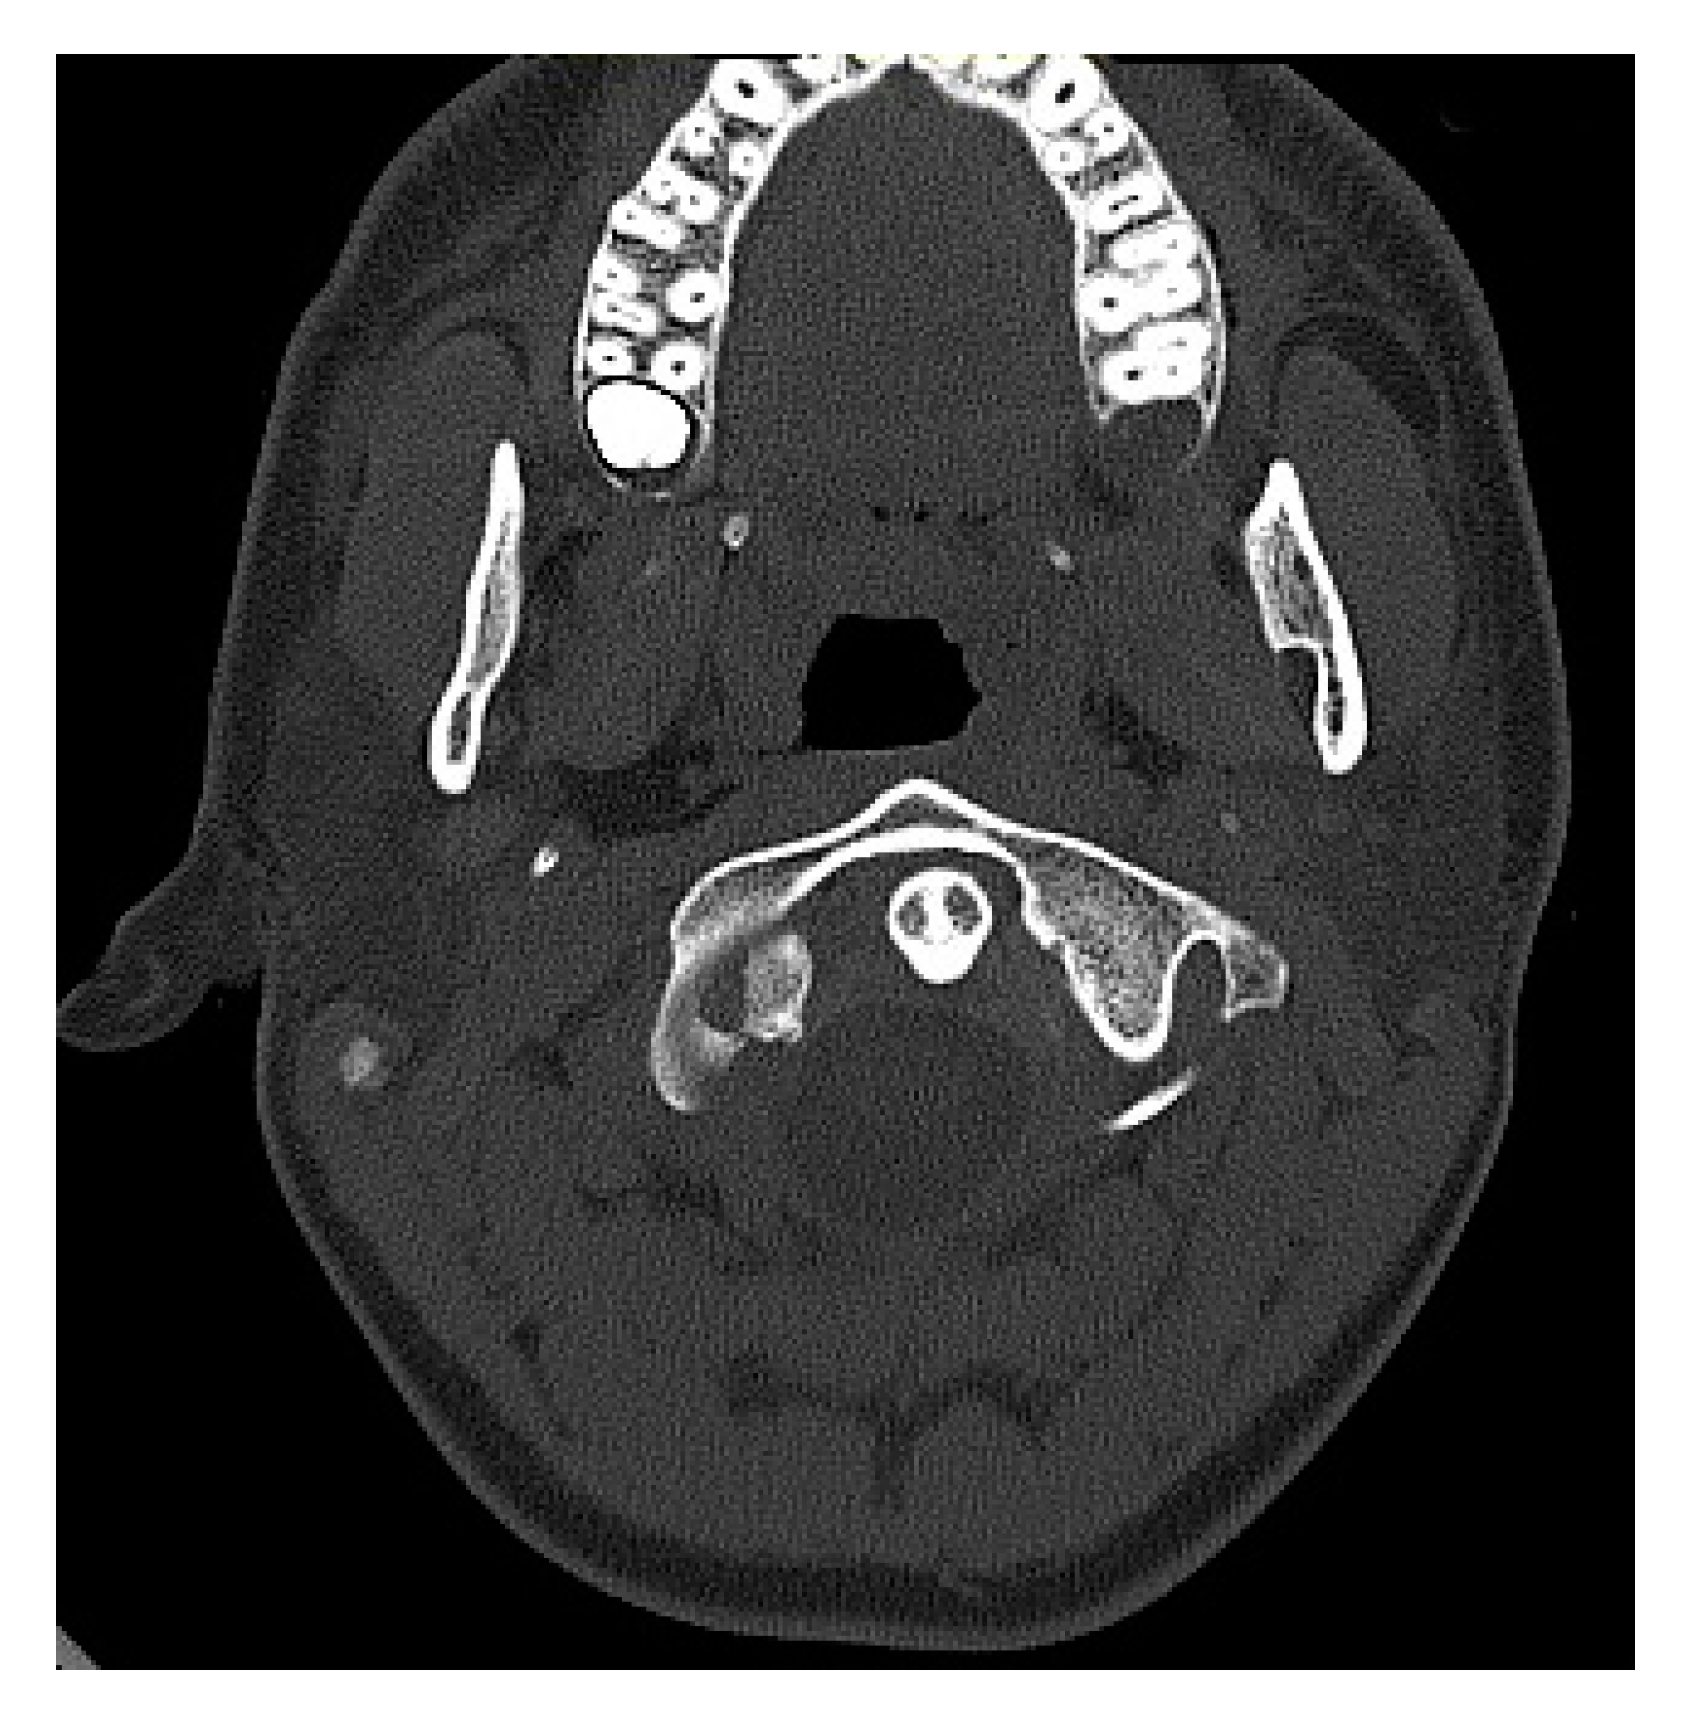

| P.P. | M | 15.2 | III (unstable) | IIB | Road traffic accident (car passenger) | Fracture frontal bone, fracture frontal sinus, contusion of frontal lobe | Halo-vest immobilization: 12.5 weeks |

| K.D. | F | 15 | III (unstable) | IIB | Pedestrian hit by car | Lung contusion, brain concussion, multiple abrasions | Halo-vest immobilization: 13 weeks |

| R.M. | F | 18 | I (unstable) | IIB | Road traffic accident (car passenger) | Pneumothorax, neurogenic vocal cord injury, post-traumatic aphasia | Halo-vest immobilization: 14 weeks |

| S.D. | M | 14.7 | III (stable) | IIA | Road traffic accident (car passenger) | Fracture of frontal bone, fracture of nasal bone, subdural hematoma | Minerva-brace immobilization |

| B.W. | F | 16 | I (stable) | IIA | Fall from a height | Fracture of frontal bone, fracture of nasal bone, subarachnoid hemorrhage, fracture of transverse process Th3-5, fracture of radius | Minerva-brace immobilization |

| M.O. | M | 16.1 | I (stable) | IIA | Bicycle incident | Fracture frontal bone, fracture maxillary sinus, fracture orbit, metacarpal fracture | Minerva-brace immobilization |